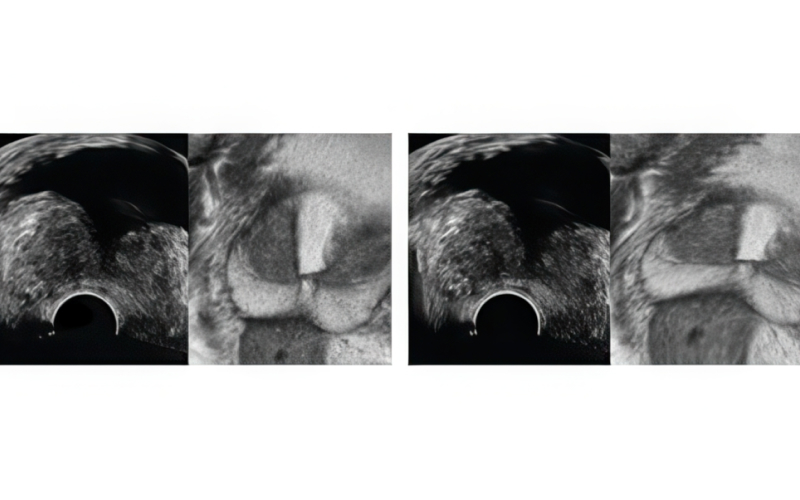

기존 검사는 병변 유무와 관계없이 12군데를 무작위로 채취해 정확도가 낮고 재검 가능성이 높았습니다. 하지만 MR 퓨전 조직검사는 병변을 직접 겨냥해 조직을 채취하므로 진단율이 크게 향상되었습니다.

최첨단 AI와 3D 융합 영상으로 진단 정확도를 혁신적으로 높인 골드만만의 특별한 조직검사입니다.